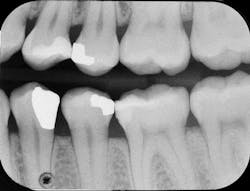

Figure 5: Radiograph for the disto-occlusal resin restoration of No. 12 showing excellent adaptation and no detectable adhesive layer

After light curing the Prime&Bond Elect for 10 seconds, the composite resin material was placed, occlusion checked, and the restoration completed (figure 4). Six months later, the patient returned for a hygiene recall appointment and reported no negative postoperative sequelae with the restoration on tooth No. 12. Bitewing radiographs were taken as a part of the exam. Not only did the restoration show excellent adaptation to the internal cavity walls, but no voids or black lines indicative of a thick adhesive layer were present (figure 5).